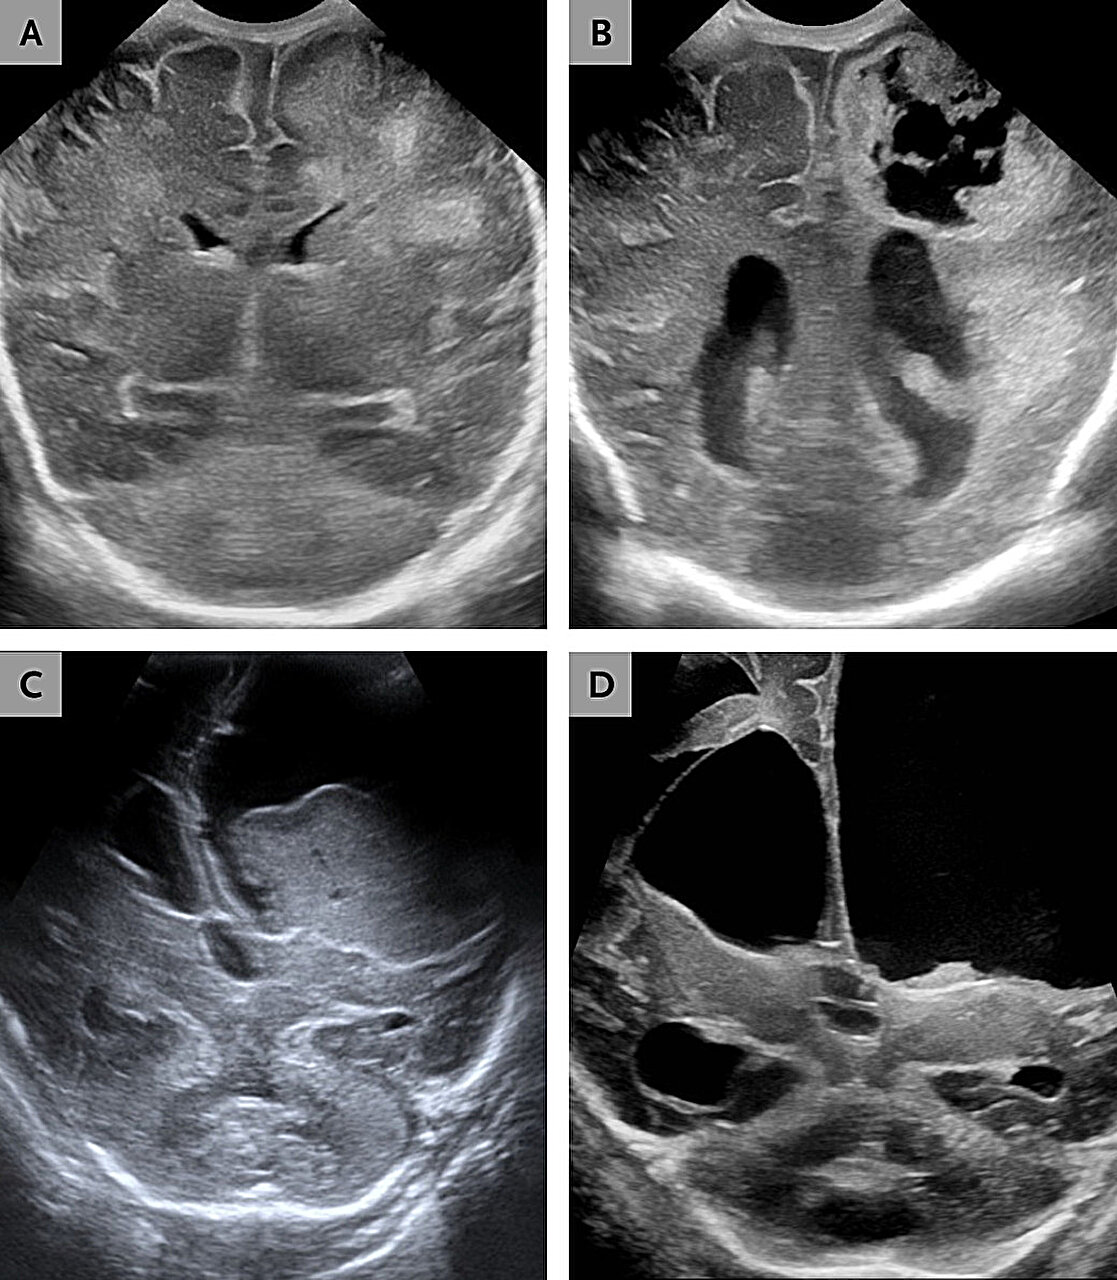

Brain imaging soon revealed the true scale of the damage. There was progressive hydrocephalus, a dangerous buildup of cerebrospinal fluid. There was encephalomalacia, softening and destruction of brain tissue. There were abscesses forming within the brain itself. Surgeons had to place a ventriculoperitoneal shunt to drain excess fluid and relieve pressure.

Again, blood and cerebrospinal fluid cultures were identified as P. thiaminolyticus. Brain imaging revealed something even more harrowing: liquefactive meningoencephalitis. In this process, brain tissue begins to dissolve into a viscous liquid.